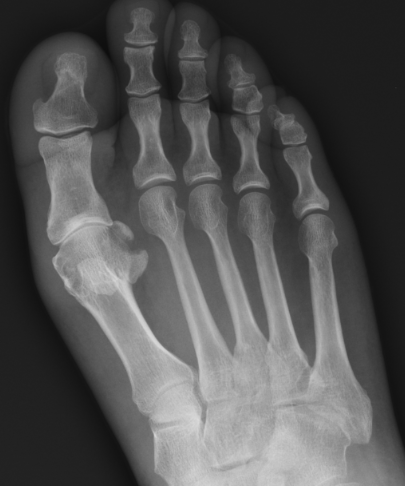

Great toe MTPJ dislocation

Pathology

Hyperdorsiflexion

Metatarsal head dislocates plantar

- tear of plantar plate / disruption bipartite sesamoid

- may buttonhole through capsule / plantar plate

Xray